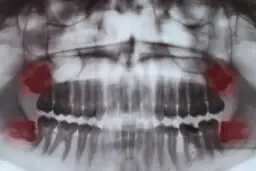

Silny ból zęba, zwłaszcza gdy mamy do czynienia z zapaleniem miazgi lub problemami z tzw. "ósemkami" (zębami mądrości), często nie ogranicza się tylko do jednego miejsca. Może on promieniować do ucha, skroni, a nawet obejmować całą stronę głowy. To zjawisko jest związane z unerwieniem obszaru głowy i szyi nerwy zębowe są ściśle powiązane z innymi nerwami w tej okolicy, co może prowadzić do błędnego odczuwania źródła bólu.